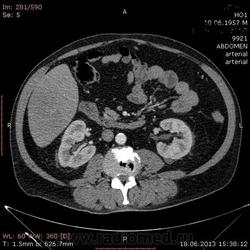

- https://radiomed.ru/sites/default/files/styles/case_slider_image/public/user/17529/img-0004-00001_3.jpg?itok=X4UUizDT

На абсцесс похоже

+1. Контраст вводили?

На мой взгляд, абсцесс.

Тоже за абсцесс.

Cпасибо , коллеги.Сегодня больного прооперировали диагноз абсцесс правой доли печени.Оказывается больной когда - то получил тупую травму живота, об этом нам не говорил.....